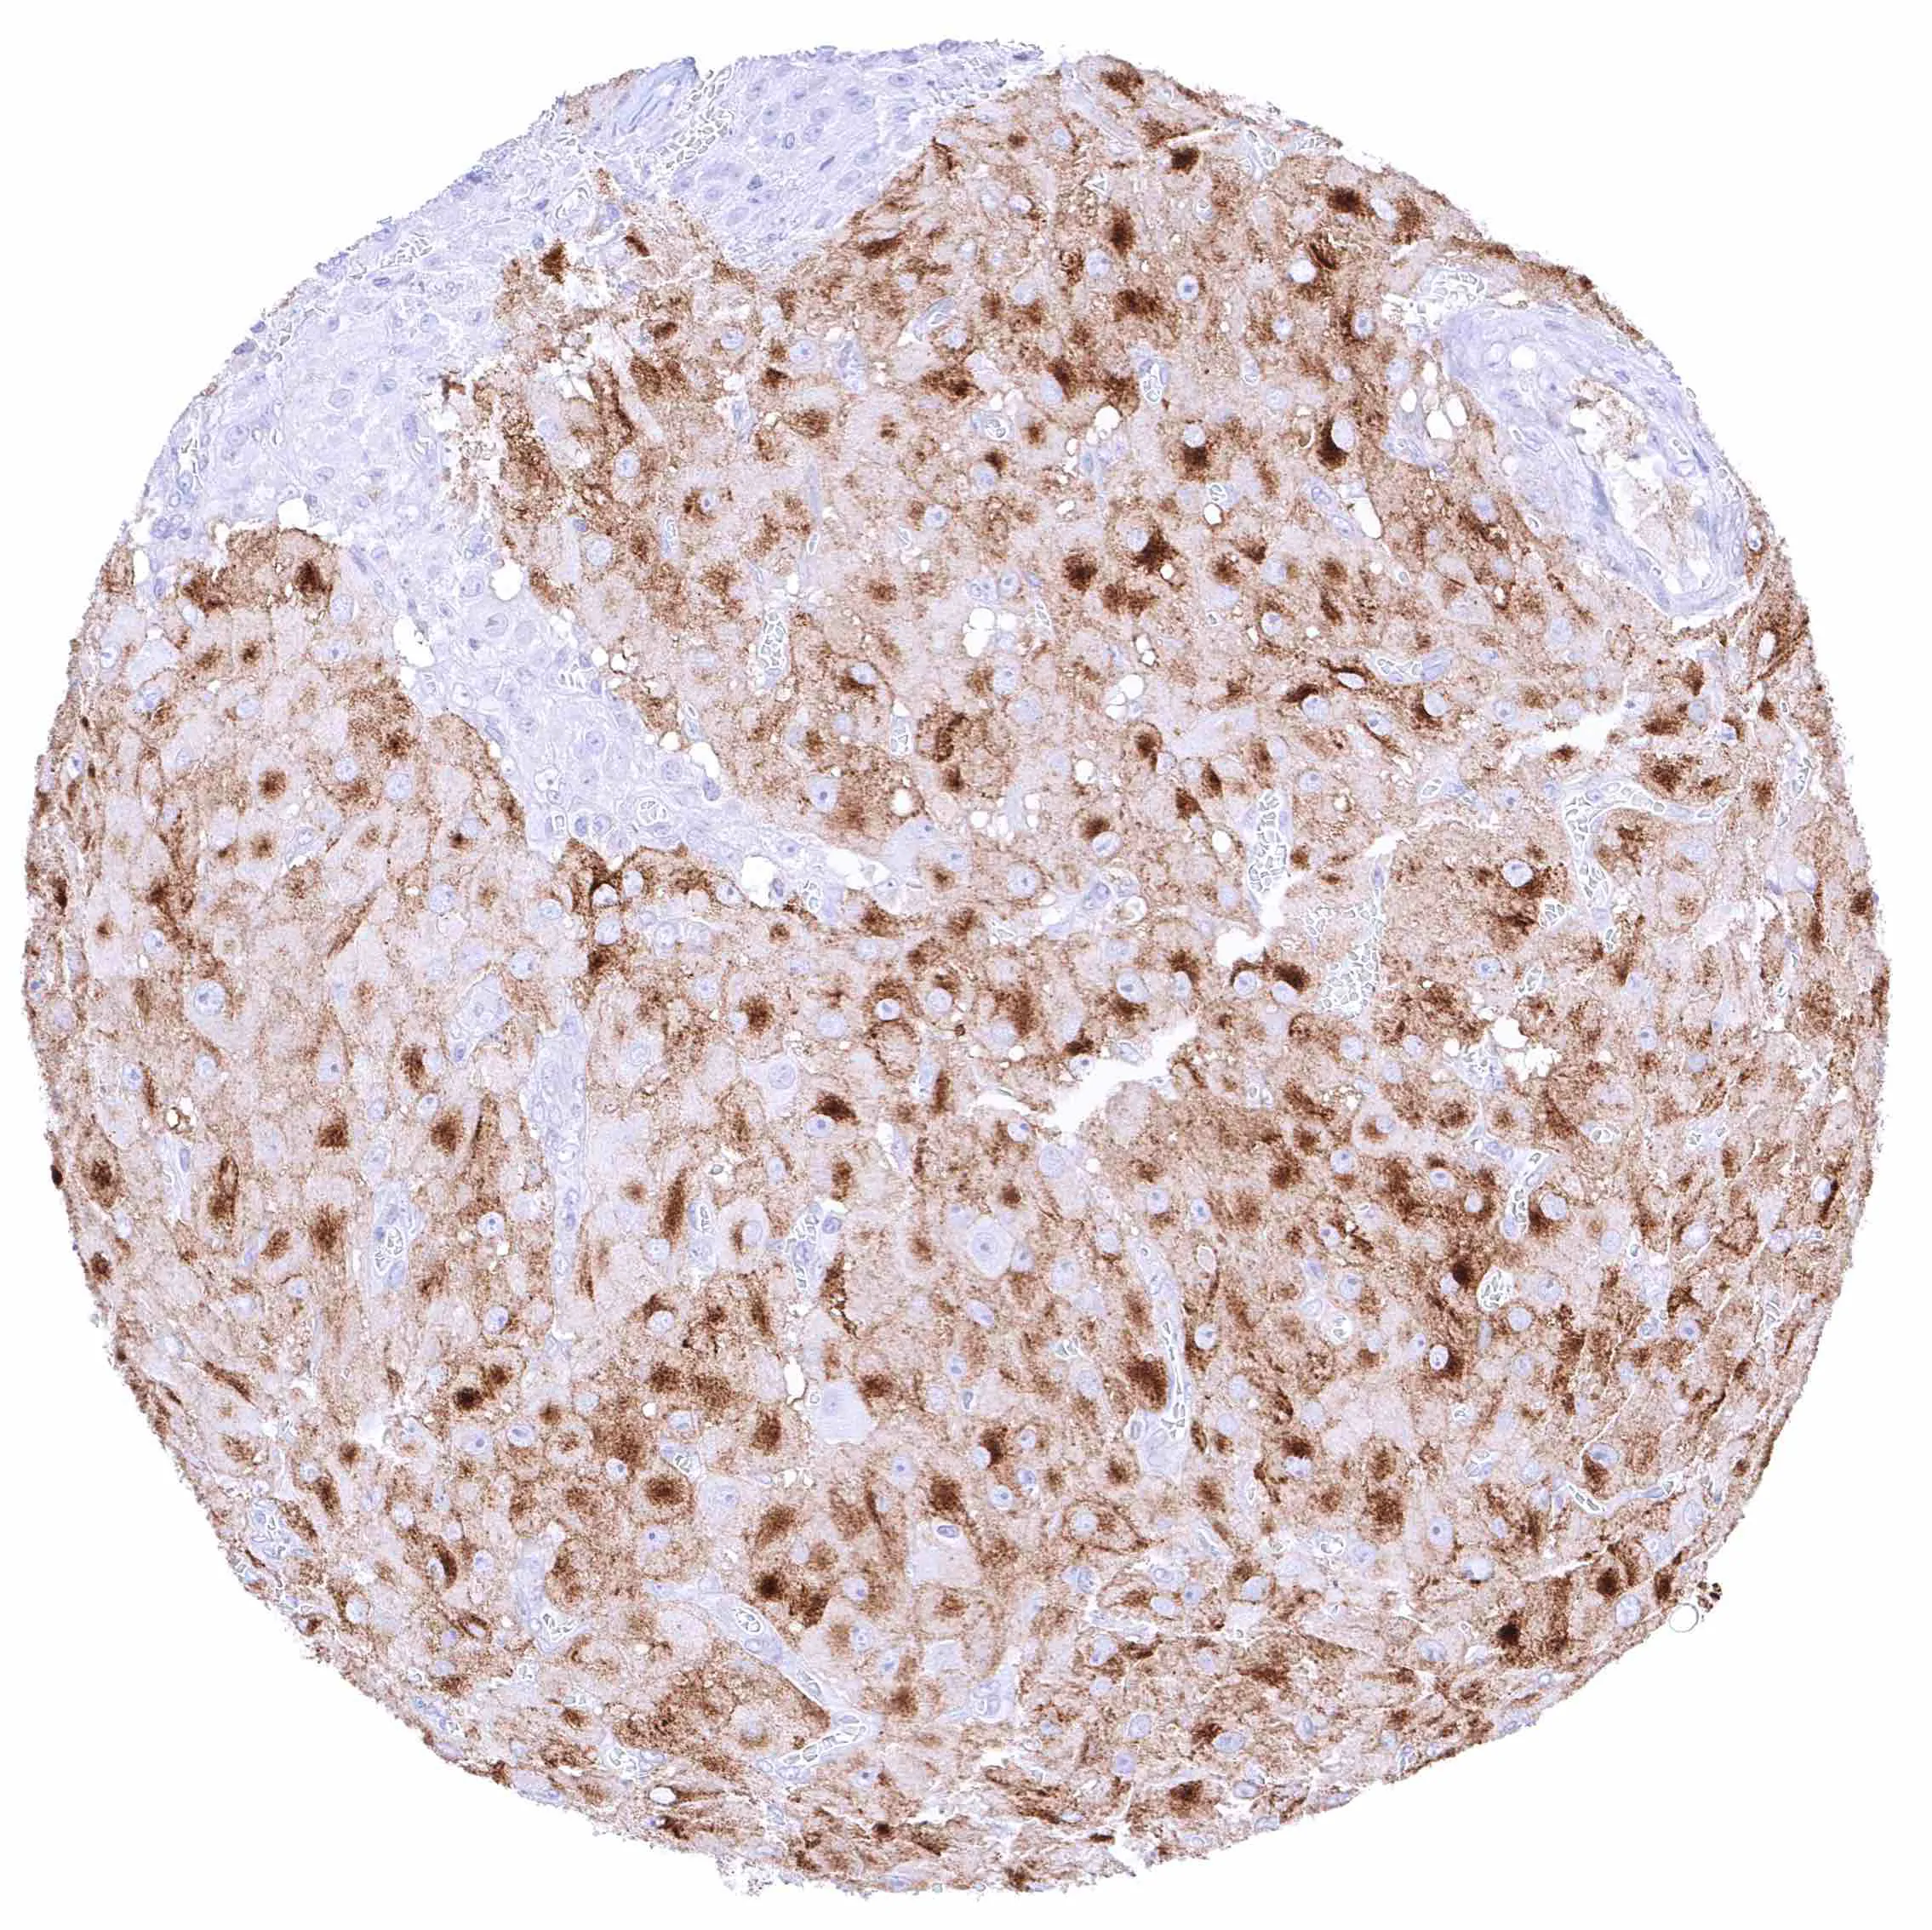

Ovary, corpus luteum – Distinct membranous and perinuclear cytoplasmic NPR-C staining of corpus luteum cells.